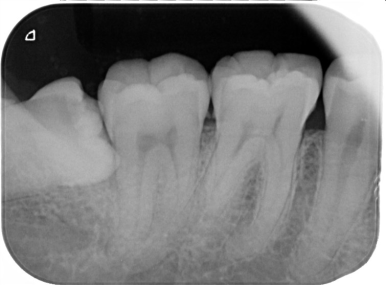

2.親知らずが虫歯になると、その手前の歯も虫歯になる可能性があります

一番右奥の親知らずは良く磨けず、虫歯になることが多いのです。早く抜いて、前の歯が虫歯にならないようにしなければなりません。

同じ症例をレントゲン写真で見たところです。親知らずが横倒しに生えていて、周りの骨を溶かしてしまっています。